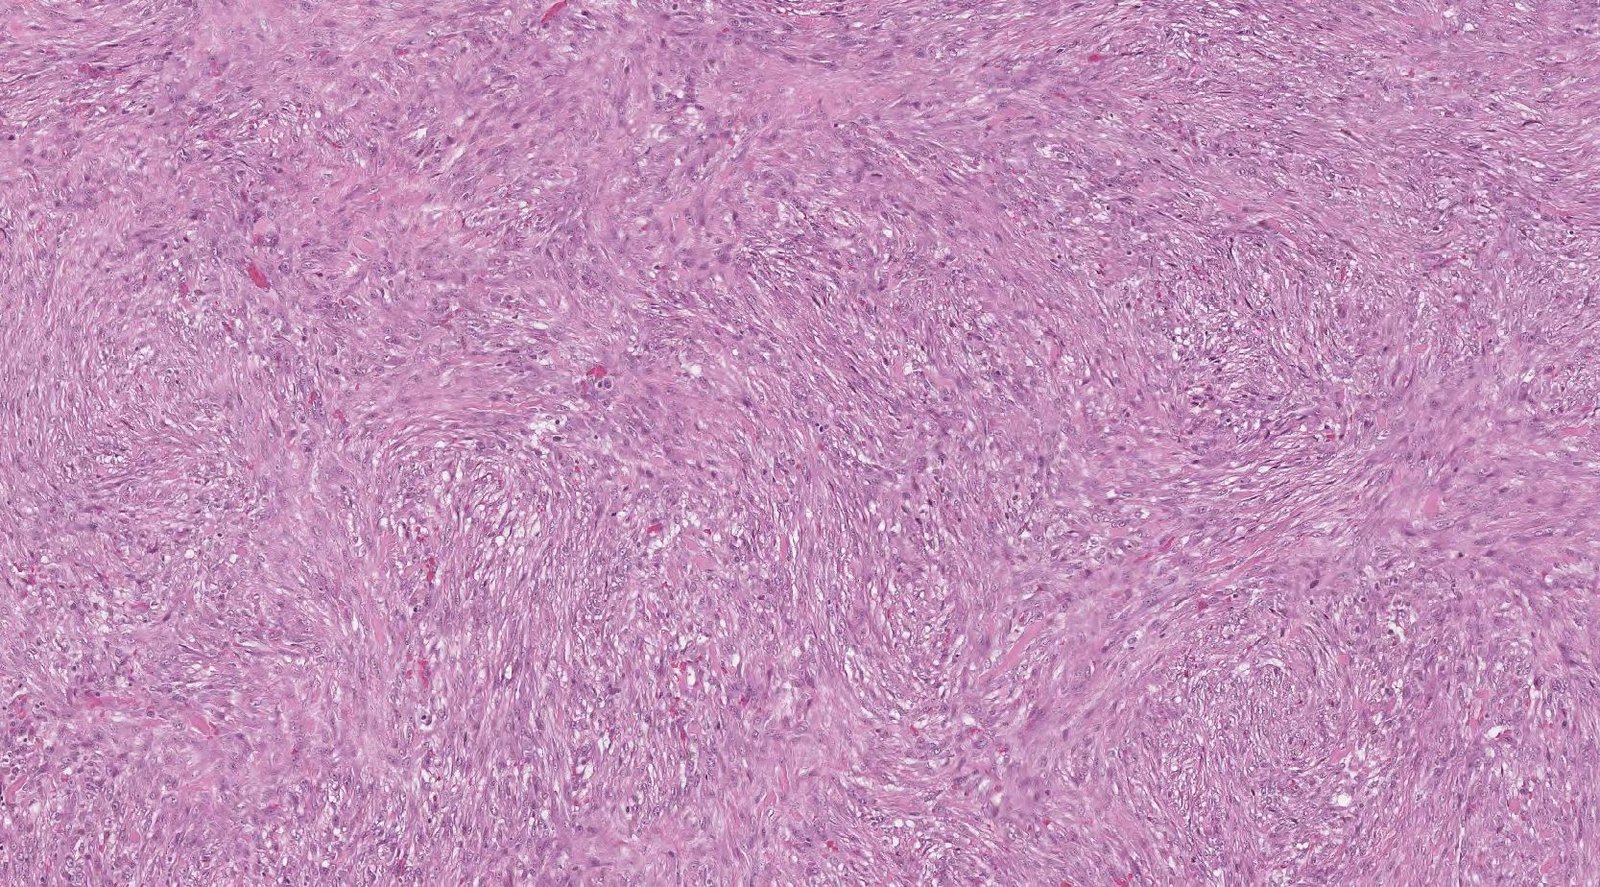

Case: WristMass

Specials to Order:

Final Diagnosis: